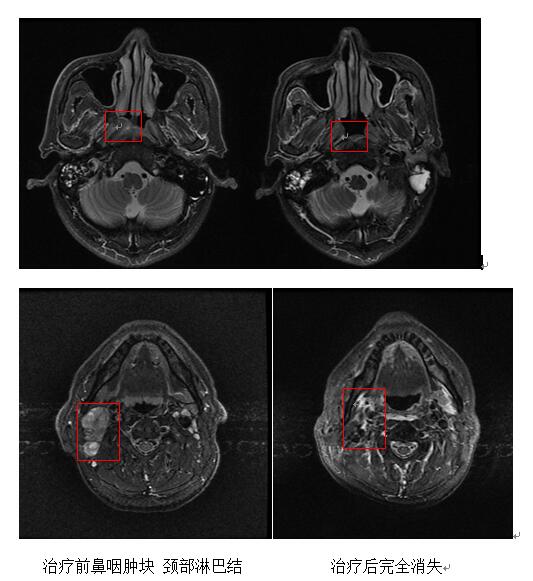

患者卢xx,男性,63岁,无意中发现右侧上颈部有一个肿大淋巴结,一个月时间约增大三分之一体积。在我院做磁共振示:考虑鼻咽癌,伴有双侧颈部淋巴结转移。做了病理活检结果确诊为:鼻咽非角化性未分化型癌,伴右颈部淋巴结转移。

我科立即予以放疗定位,制定放疗靶区,行根治性放疗,并做了同步化疗,同时予以中药汤剂、中药贴敷以及中药外洗等特色治疗,减轻放化疗副反应,预防放化疗并发症,提高生活质量。治疗过程顺利,放化疗结束后,鼻咽部肿块及颈部肿大淋巴结完全消除,症状完全消失。已随访20个月,病情稳定,未发现复发转移,患者完全恢复正常生活。